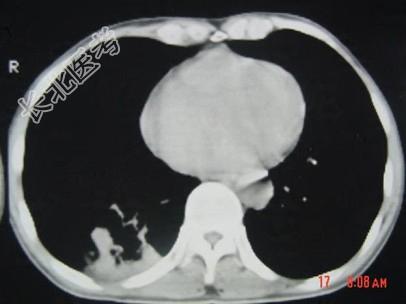

- 单项选择题男,40岁, 胸背疼痛一周,消瘦一月, CT检查如图,最可能的诊断为 ( )

A、右下肺结核

B、右下肺脓肿

C、右下肺炎

D、右下肺肺泡癌

E、右下肺炎性假瘤